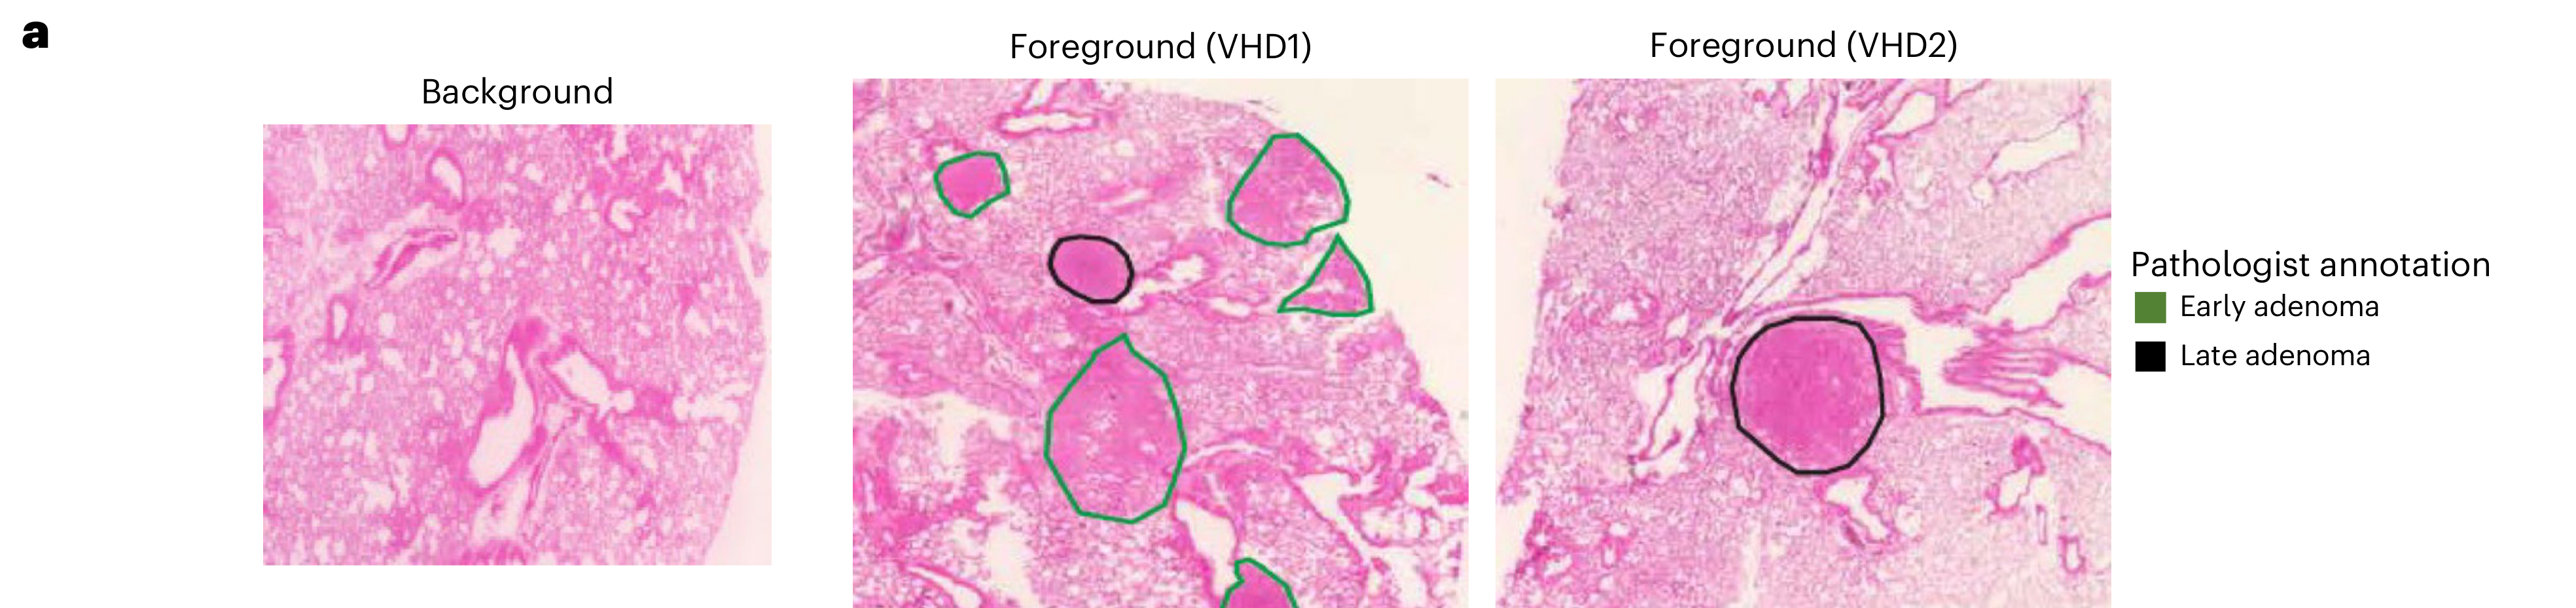

Jiang X. et al. - 2024

iIMPACT: integrating image and molecular profiles for spatial transcriptomics analysis

Modality

How are pathologist-defined tissue regions distributed across a cancer tissue section?

Partial

Histological image

Highlighting

Spatial : Physical

None (Item-level)